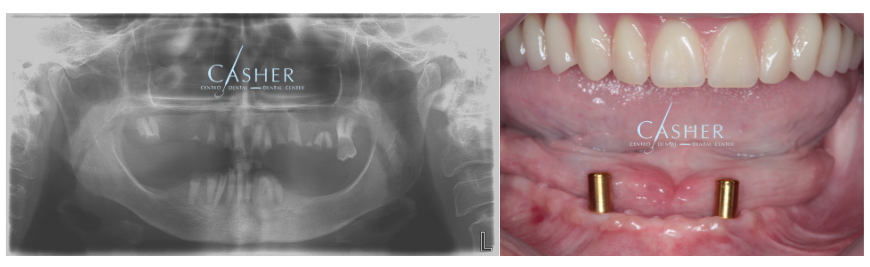

El caso clínico: paso a paso

Nuestro paciente llegó buscando una alternativa a la prótesis tradicional. Le realizamos una planificación con diagnóstico digital y colocamos dos implantes inferiores, preparados para el sistema Locator. A continuación te mostramos algunas imágenes del proceso:

- Implantes colocados en mandíbula inferior, perfectamente integrados.

- Adaptación de la prótesis superior existente.

- Prueba y ajuste del sistema Locator.

- Resultado final: prótesis inferior estable, cómoda y estética.

- El resultado no solo fue funcional: la paciente volvió a sonreír con seguridad.